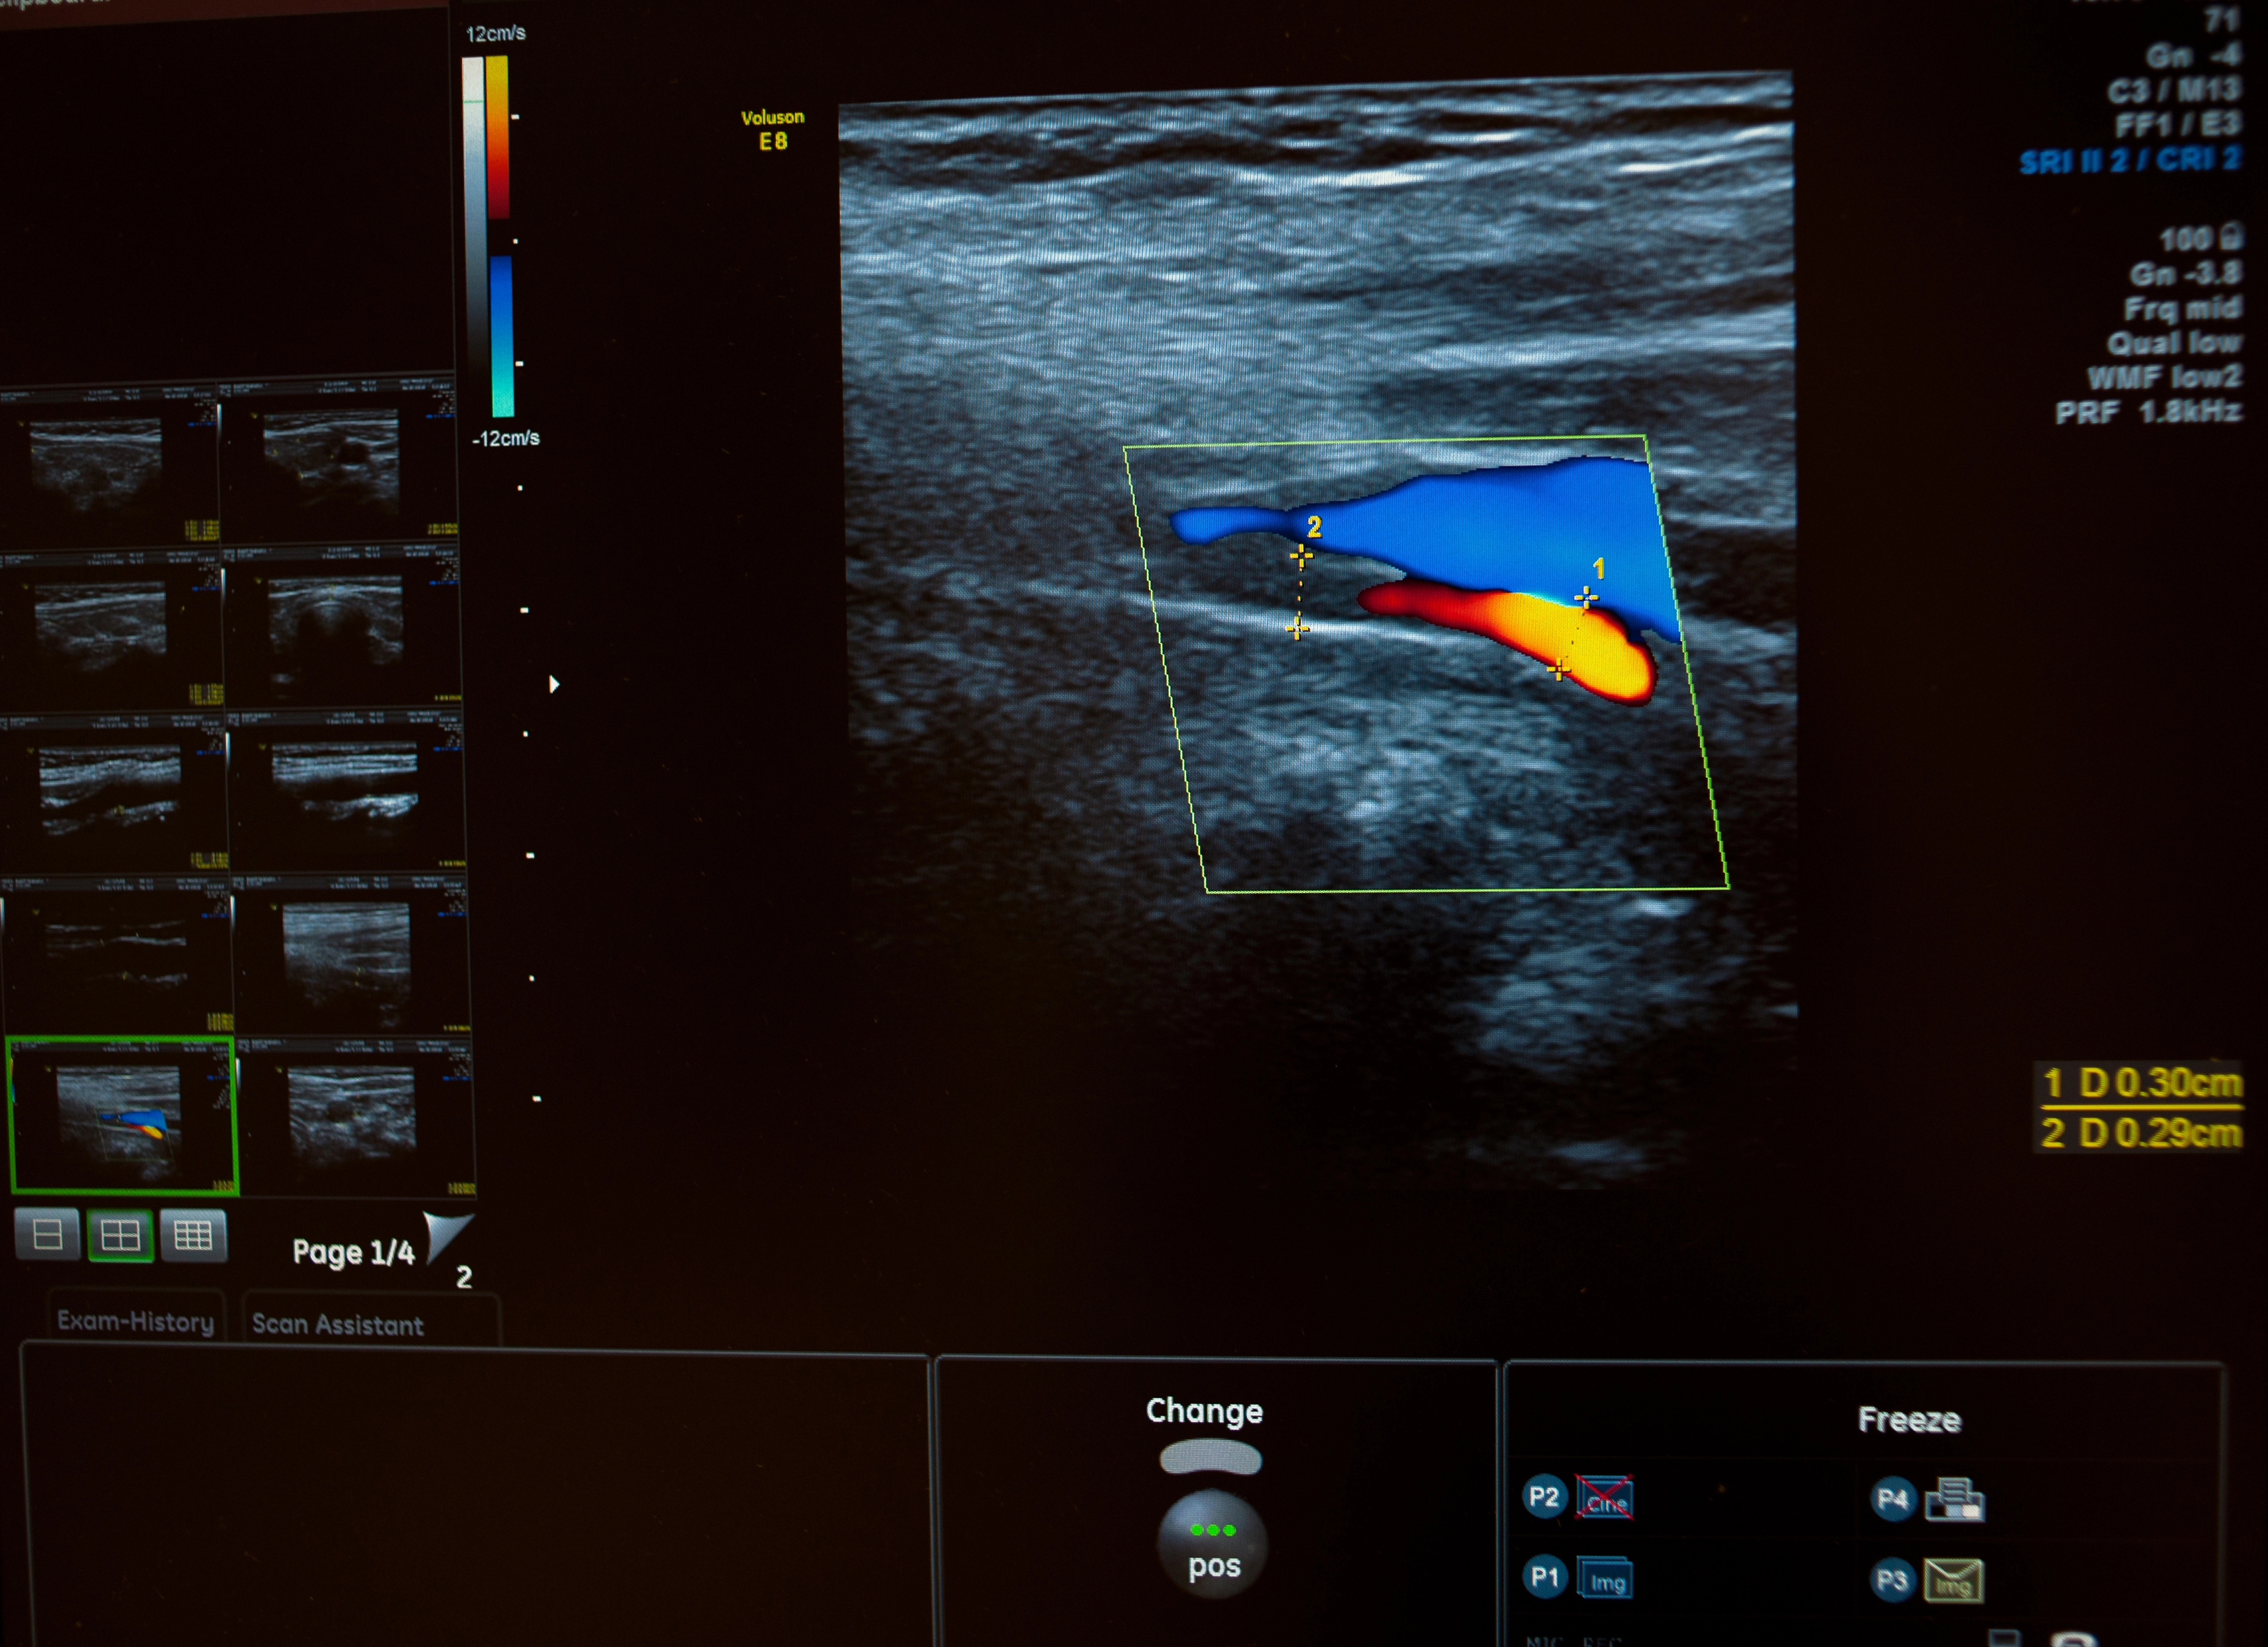

При диагностике определяется однородность структуры органа, размер, положение и другие нюансы.